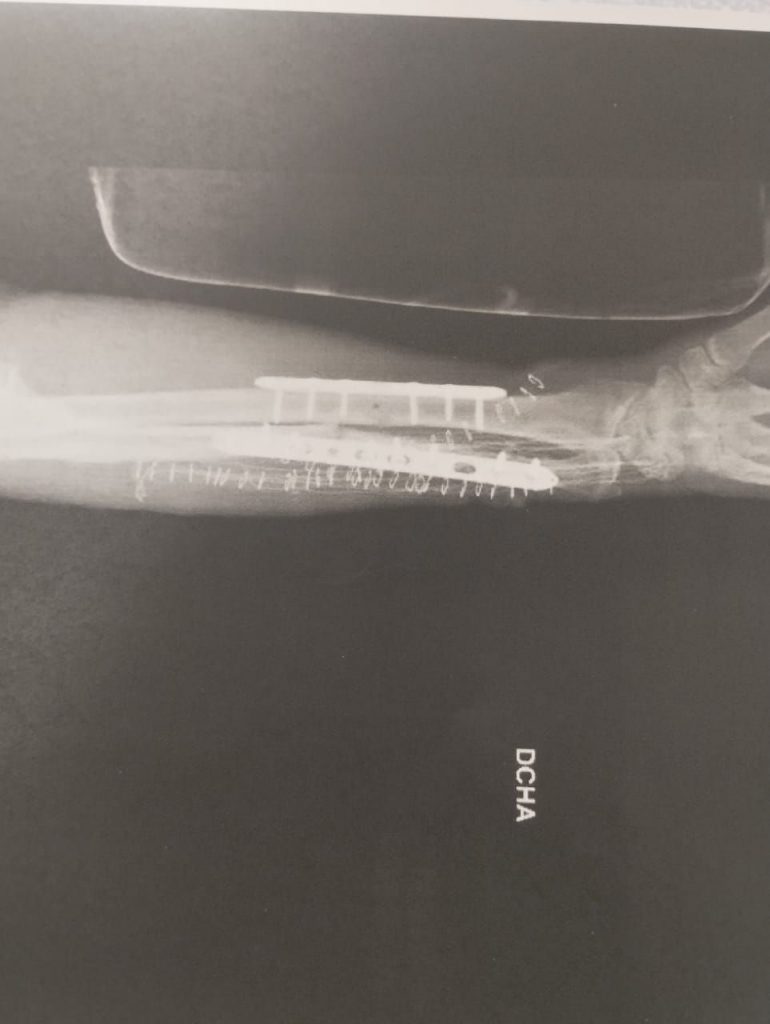

Este señor psicópata tiene orden de alojamiento del local y del propietario del local desde ese día. A día de hoy, 18 de enero, ha quebrantado la orden por tres veces, y ha sido detenido otras tres veces, y puesto en libertad, creando el caos en dicho local y agrediendo al propietario del local con una barra de hierro, partiéndole el brazo por dos lados, ocasionándole dos fracturas muy graves y debiendiendo ser operado con urgencia, una operación que ha conllevado cuatro horas.